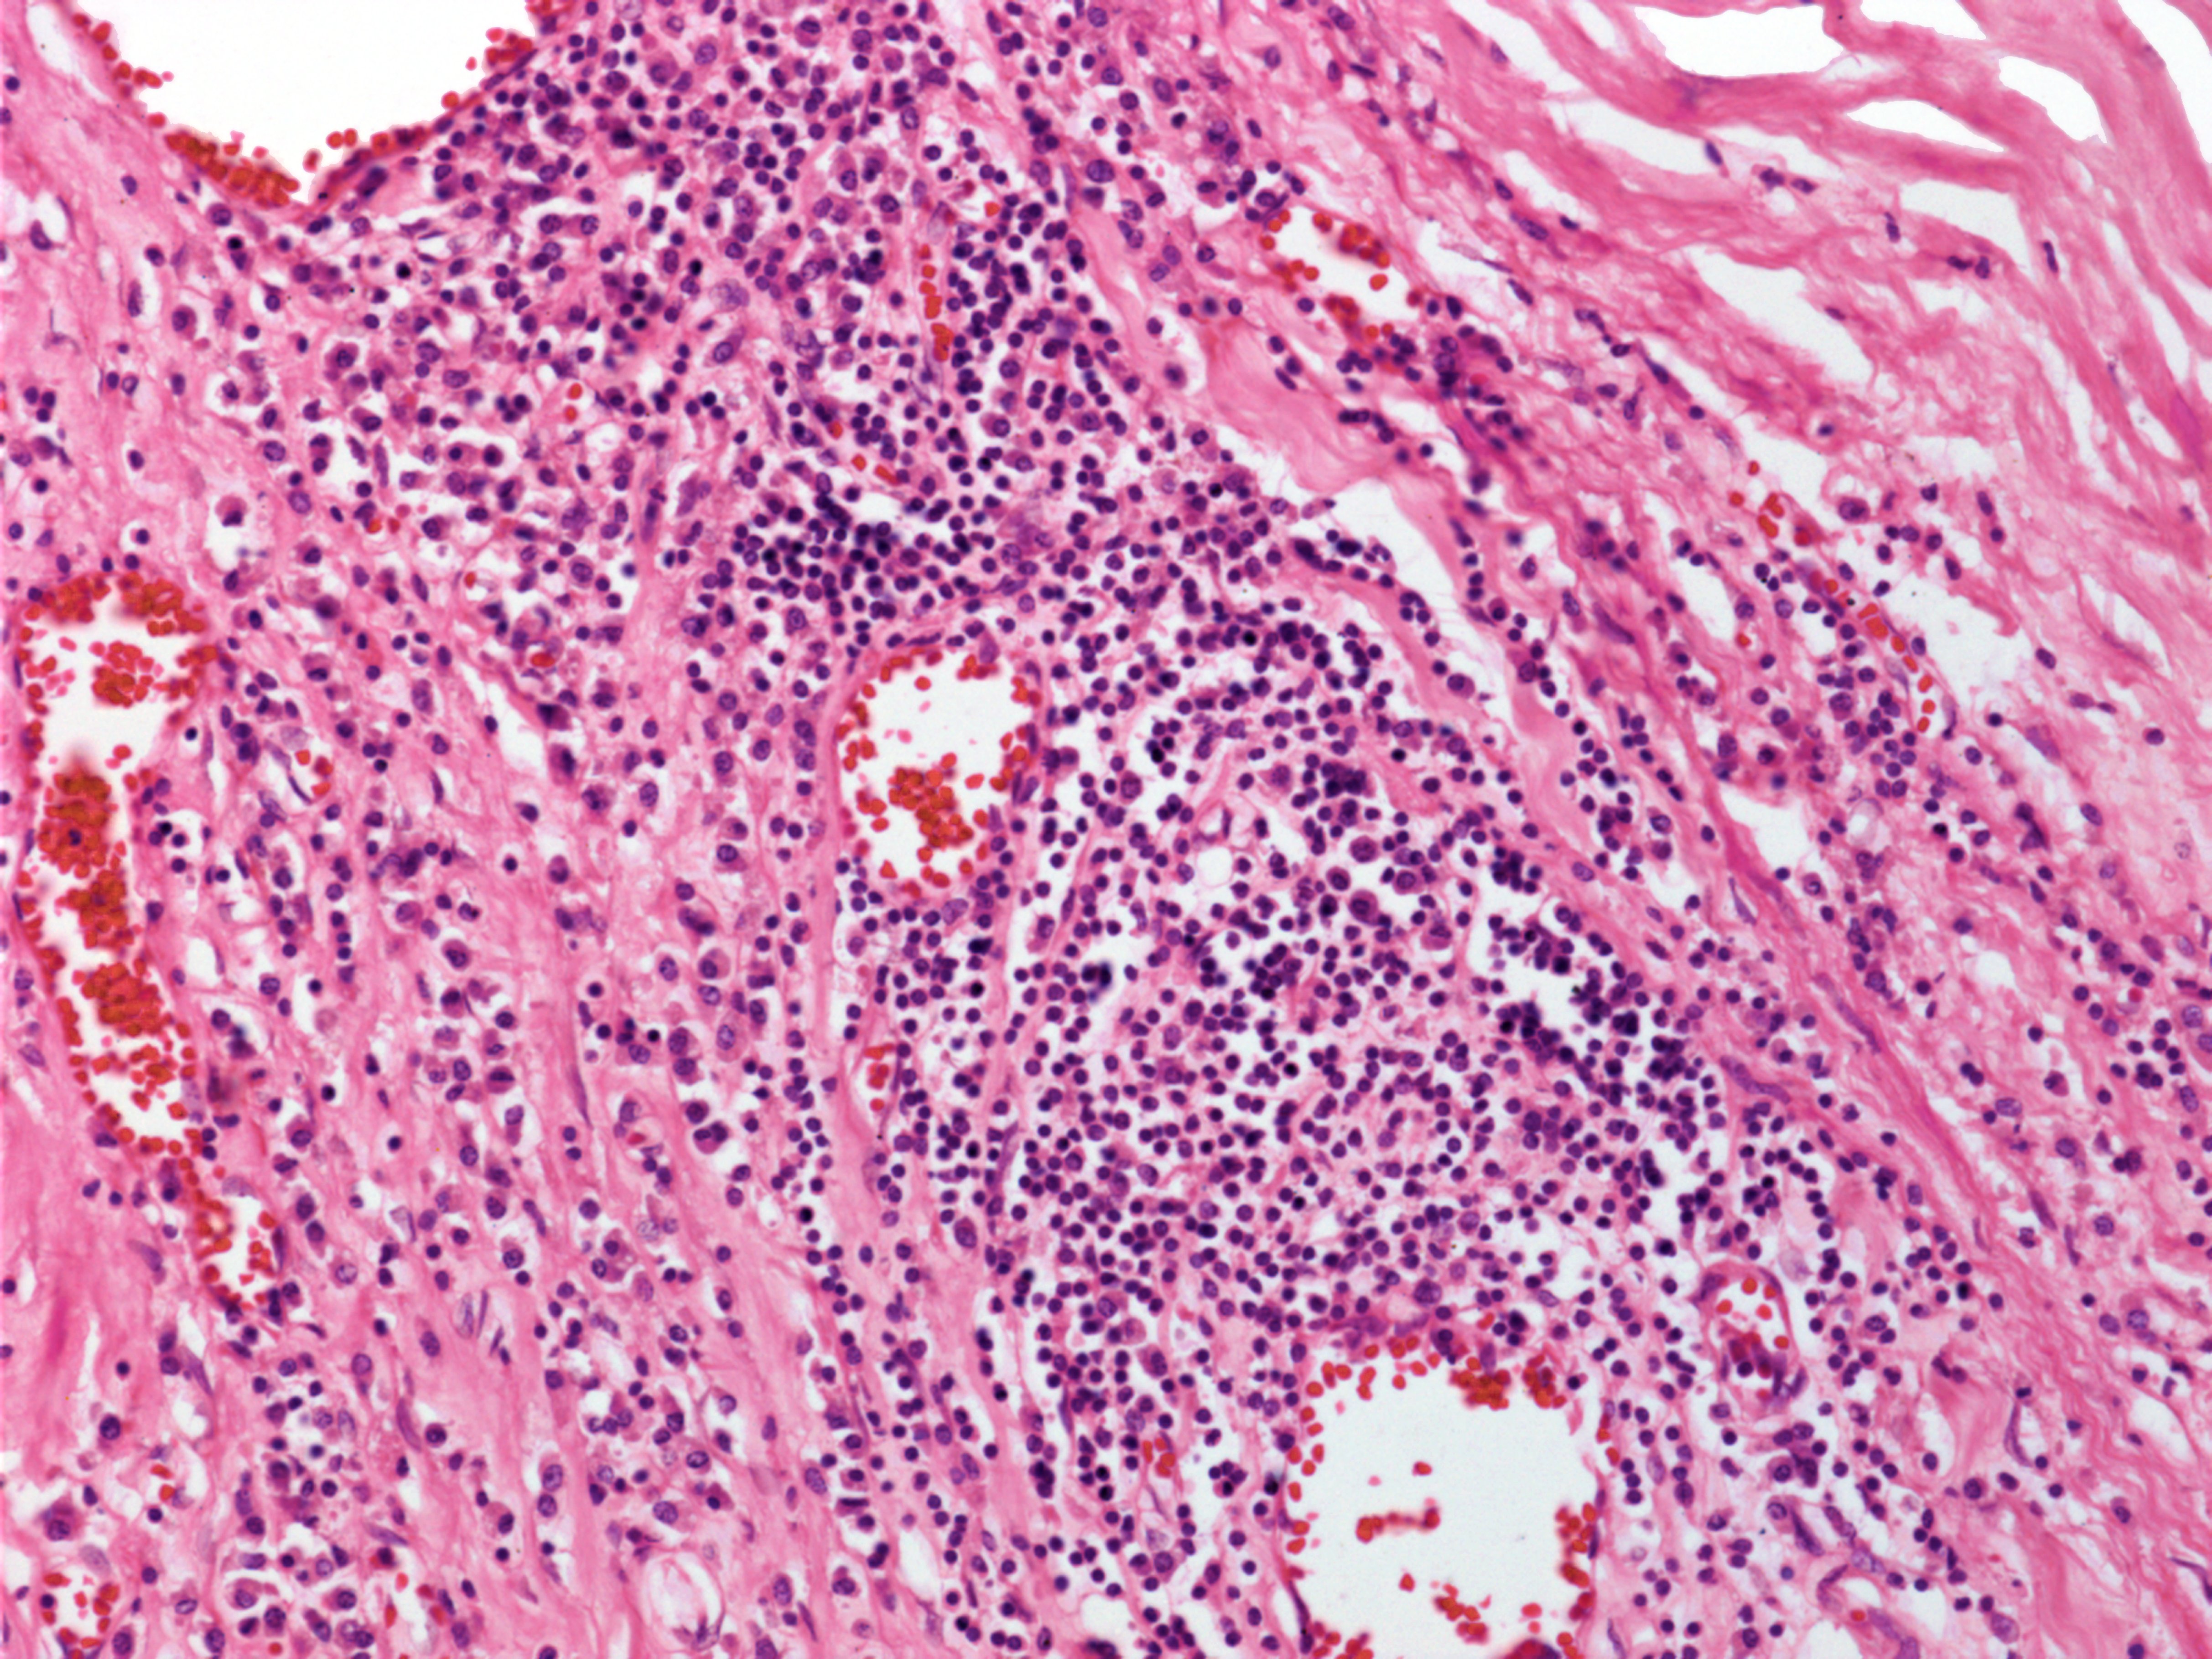

Syphilis is a bacterial disease that surfaces as genital sores but can ultimately lead to severe symptoms and death if left untreated.